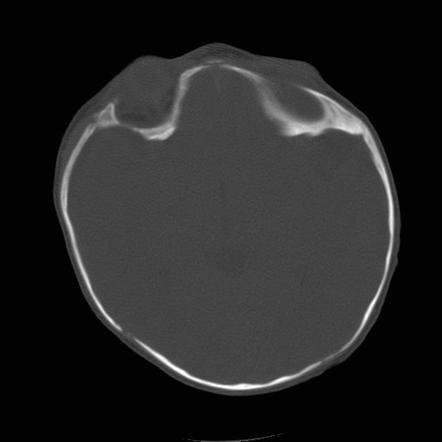

Sagital synostosis, syndrome

A

Scaphocephaly (also known as dolichocephaly) is the MOST COMMON FORM of craniosynostosis, where premature closure of the sagittal suture results in an impediment to the lateral growth of the skull while anteroposterior growth continues, producing a classic elongated, yet narrow, skull.

Marfan syndrome (both are tall and skinny)

Normal IQ. No hydrocephalus.